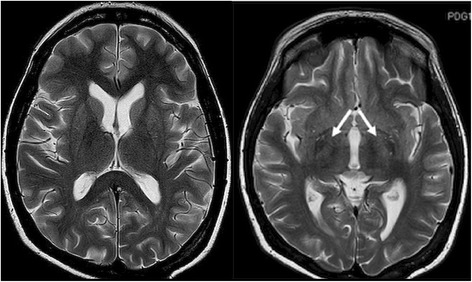

Psychiatric examination was performed pointing to brain dysfunction. The administration of tiapride, thiamine and piracetam was initiated with no resulting benefits. A noncontrast CT brain scan was performed to exclude the structural pathology of the brain with negative result. Because of progressive worsening of consciousness and the development of tremor, neurologists were consulted. In addition to mental disturbances, signs of severe, symmetric Parkinsonism were present - with resting tremor of the chin and all four limbs (MDS-UPDRS III- 4), brady/hypokinesia (MDS-UPDRS III - 3) and rigidity (MDS-UPDRS III –1) [4] revealed by neurological examination. Furthermore, clinical signs of severe postural instability (MDS-UPDRS III -4) were observed. No pyramidal signs or impairment of other systems (oculomotoric, bulbar, cerebellar) were revealed by neurologic assessment. A brain MRI was performed that revealed subtle hyperintensities in T2- sequences in basal ganglia bilaterally without the abnormalities found in the diffusion weighted images (DWI sequences) in the MRI (Fig. 1). Thus, in regard to the chronological course of clinical symptoms related to liver transplantation and subsequent immunosuppressive treatment, we suggested the onset of Parkinsonism was due to tacrolimus-induced encephalopathy. The administration of amantadine, levetiracetam (1000 mg/day) and clonazepam (initial dose 1.5 mg/day) was initiated, with a satisfactory reduction of tremor; and with a positive effect on rigidity and hypokinesia. The tacrolimus blood concentration was above normal levels (21.7 ng/ml, normal value < 20 ng/ml) - the dose was therefore reduced (8 mg/day) and 3 days later, tacrolimus was changed to less toxic sirolimus (Rapamune 1 mg, GBR) according to standard treatment options. One week after the treatment modification and 2 weeks after the first onset of parkinsonian signs, the patient’s tremor and brady/hypokinesia markedly improved (MDS-UPDRS III- 1 and MDS-UPDRS III- 1). No clinically detectable sign of rigidity was found after treatment modification either. Furthermore, no cognitive impairment was observed. Only a mild degree of rest tremor (MDS-UPDRS III- 1) was present in this patient at the time of discharge from the hospital. Due to further improvement of extrapyramidal symptoms, neurological medication was reduced gradually in 3- month follow-up period checks. No clinical deterioration or worsening of the condition was observed during this period. The current treatment includes administration of sirolimus (4 mg/day) with concomitant use of methylprednisolone (2 mg/day) and mycophenolate mofetil (500 mg/day). The sirolimus blood concentration achieved the therapeutic range and no relevant adverse events were observed. No additional treatment of neurological or psychiatric symptoms was needed.

Fig. 1.

Symmetrical T2-hyperintensity of basal ganglia on MRI (white arrows)